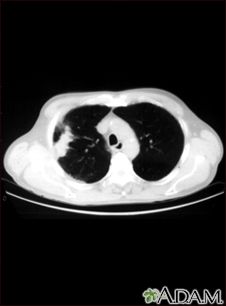

Lung with squamous cell cancer - CT scan